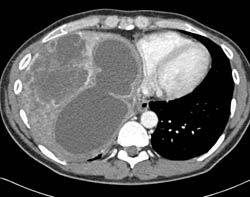

Biliary Cystadenocarcinoma